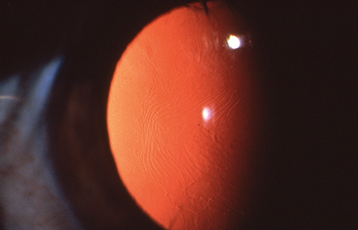

Changes at the level of Descemet membrane, including vesicles arranged in a linear or grouped pattern, diffuse blotchy gray haze, or broad bands with irregular, scalloped edges (see Figure 4.26.9). Iris abnormalities, including iridocorneal adhesions and corectopia (a decentered pupil), may be present and are occasionally associated with corneal edema. Glaucoma may occur. See 8.14, Developmental Anterior Segment and Lens Anomalies/Dysgenesis, for differential diagnosis. Treatment includes management of corneal edema and corneal transplantation for severe cases.